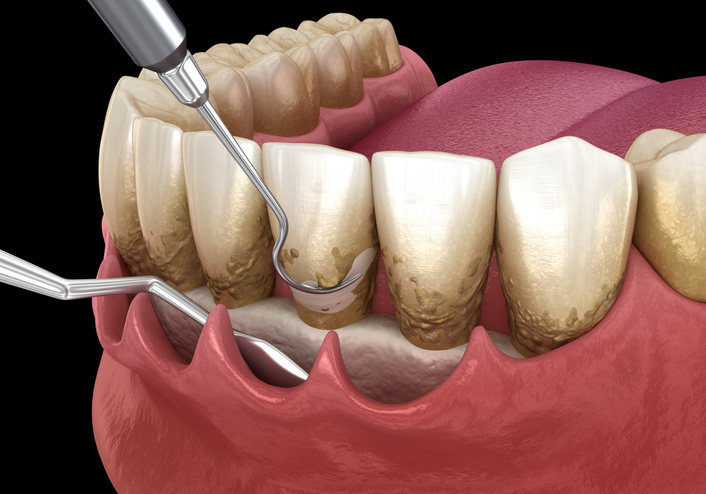

- Scaling and root planing (deep cleaning): Removal of subgingival plaque and tartar, and smoothing of tooth roots. This is a more intensive cleaning procedure, akin to a “deep bath” for your teeth and gums.